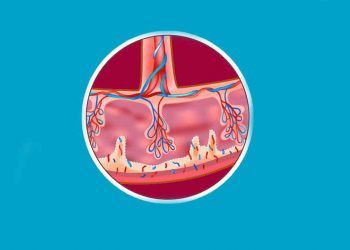

Villi Koryalis, koryonun döl yatağı mukozasında gönderdiği maternal fetal kan değişimini sağlayan koryon zarının dış yüzeyindeki mikroskobik parmak biçiminde olmak...

Villöz Plasenta, koryondaki villusların aşırı biçimde gelişmesiyle belirgin plasenta biçimine denir. Villous placenta

Villus, sarkan saç veya püskül, kıl demeti, kılsı çıkıntı, parmak biçimindeki küçük çıkıntılara denir.